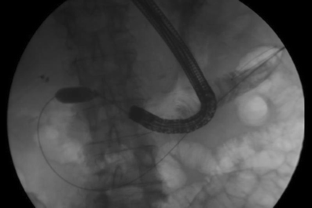

Figure 1

Figure 2

Figure 3

Figure 4

Figure 5